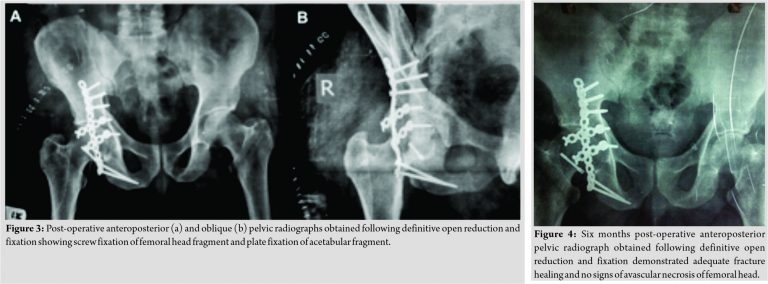

Reduction of hip dislocation was attempted in emergency room but found to be unstable. Patient was kept on skeletal traction for 24–48 h and subsequently planned for open reduction and internal fixation. Kocher-Langenbeck approach was used which allowed direct visualization of the dorso-cranial part of acetabulum. Femoral head fracture was fixed using Herbert screw and recon plate and spring hook plates were used to fix acetabular fracture fragment and to stabilize the reduction (Fig. 3). Post-operative period was uneventful. Hip joint was kept in abduction and slight external rotation for optimal healing while allowing controlled flexion and extension. Hip muscles strengthening exercises were started slowly and gradually as tolerated by the patient. Bony union was noted 12 weeks postoperatively (Fig. 4) and after 14 weeks patient was able to sit and squat easily.

In follow-up, patient was evaluated clinically and radiologically. There were no signs of avascular necrosis and arthritis after 5 years of follow-up. Patient had rewarding outcomes in the form of adequate range of motion and painless ambulation (Fig. 5).